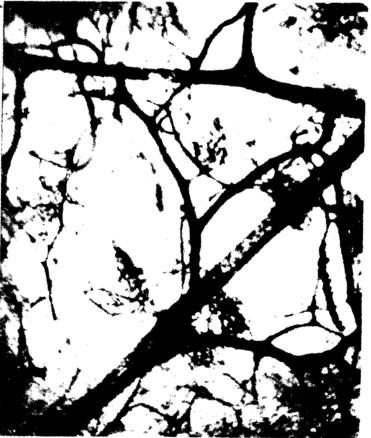

三、肩胸区皮瓣血管构筑

3例尸体肩胸区取材的皮肤分层透明标本观察所见:皮肤动脉在穿过浅筋膜时分支较少,一旦到达真皮下层则立即分成数条分支呈水平方向展开,并与相邻动脉分支吻合成网,形成真皮下血管网(图一),该血管网没有静脉伴行。来自乳头下静脉网的静脉支及浅筋膜层的静脉,在真皮下动脉网深面汇合成非伴行性浅静脉网或较粗大的浅静脉干(图二)。乳头下微静脉的管径大(30~60um)而密集。浅筋膜内与微动脉伴行的静脉管径细小(10~20um)稀疏,在脂肪间隔处吻合较少,但其汇入的浅筋膜层非伴行静脉则管径很粗大。

图二、 人体胸肩峰皮瓣真皮下动脉网深面的较粗大浅静脉干 |